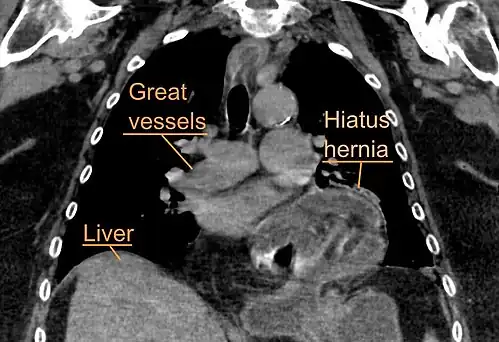

The diagnosis of a hiatal hernia is typically made through an upper GI series, endoscopy, high resolution manometry, esophageal pH monitoring, and computed tomography (CT). Barium swallow, as in the upper GI series, allows the size, location, stricture, and stenosis of oesophagus to be seen. It can also evaluate the oesophageal movements. Endoscopy can analyse the esophageal internal surface for erosions, ulcers, and tumours.

Meanwhile, manometry can determine the integrity of esophageal movements and the presence of esophageal achalasia. pH testing allows the quantitative analysis of acid reflux episodes. A CT scan is useful in diagnosing complications of hiatal hernia, such as gastric volvulus, perforation, pneumoperitoneum, and pneumomediastinum.[8]

A hiatal hernia as seen on CT -

A large hiatal hernia as seen on CT imaging -